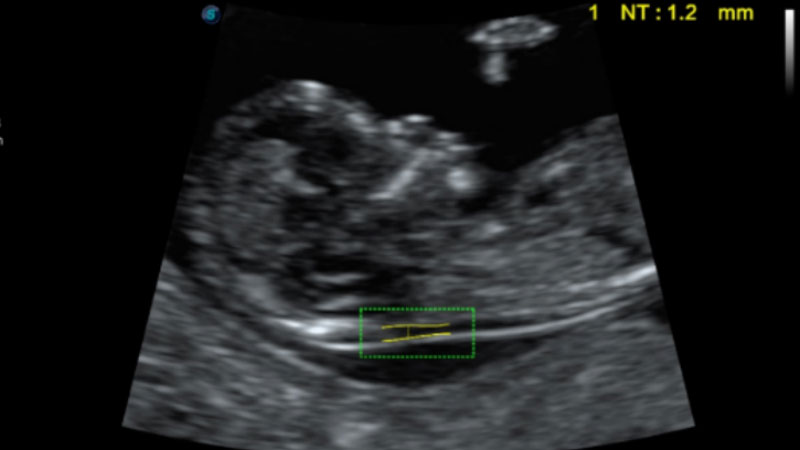

S-Fetus基于大數(shù)據(jù)深度學(xué)習(xí)算法,能夠幫助您在產(chǎn)前篩查過程中智能識(shí)別胎兒標(biāo)準(zhǔn)切面、自動(dòng)測(cè)量并錄入報(bào)告。一個(gè)按鍵,即可智能、精準(zhǔn)、高效地獲取胎兒生理指標(biāo),極大簡(jiǎn)化您的產(chǎn)科檢查操作。

可快速對(duì)產(chǎn)科掃查切面完成胎兒生理學(xué)參數(shù)的自動(dòng)測(cè)量,減少操作者按鍵次數(shù),大幅提升檢查效率。

自動(dòng)識(shí)別頸項(xiàng)透明層并獲得NT值,為早孕胎兒畸形篩查提供有效測(cè)量工具,提高診斷效率和診斷信心。